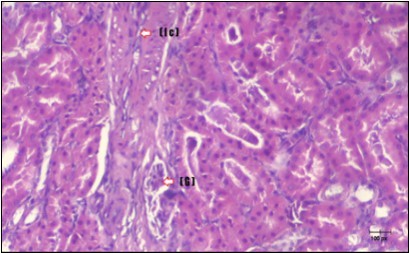

Kidney Histopathological Observations

Kidney sections of diabetic rats showed an increase in mesangial cell and matrix of glomeruli with increase in glycogen deposition and hyalinization of arterioles with thickened basement membranes of proximal and distal convoluted tubules. These changes will lead to progressive reduction in the filtration surface of the glomeruli 35. Histological examination of the kidney of the control rats showed normal structure of renal glomerular. The proximal and distal tubules were lined with normal epithelium (Figure 13). The diabetic rats showed tubular casts, inflammatory cellular infiltration and glomerular atrophy (Figure 14). Kidney of rats in groups (3 and 4) showed some glomeruli return to be normal (G). Focal tubules casts (T) in Fenugreek group and some normal tubules in the Glimepiride group with no inflammatory cellular infiltrate in both groups (Figure 15 and Figure 16). However, kidney of rats in group (5) showed normal glomerular (G), normal tubules (T) with no tubular casts (Figure 17).

Figure 14.Photomicrogragh of kidney section of diabetic rat showing a trophy of Bowman,s capsules and damage of glomeruli (arrow) and damage of distal and proximal tubules with congested blood vessels (star) . (H&E) (100Px).

Figure 15.Photomicrogragh of kidney section of treated rat with Fenugreek showing improvement of Bowman,s capsules with normal glomerular (arrow) and nearly return of distal tubules (dashed –arrow) and proximal tubules (star) (H&E) (40xX).

Figure 16.Photomicrogragh of kidney section of treated rat with Glimepiride showing improvement of Bowman,s capsules and partial improvement of glomerulir (arrow) and completely return of distal tubules and proximal tubules to the normal shape with wide urinary space. (H&E) (40X).

Figure 17.Photomicrogragh of kidney section of treated rat with both Fenugreek and Glimepiride showing improved cortical tissue with most of both Bowman,s capsules (arrow) and proximal tubules (dash-arrow) with nearly normal structure .Note distal tubules still suffering (star). (H&E) (40X).